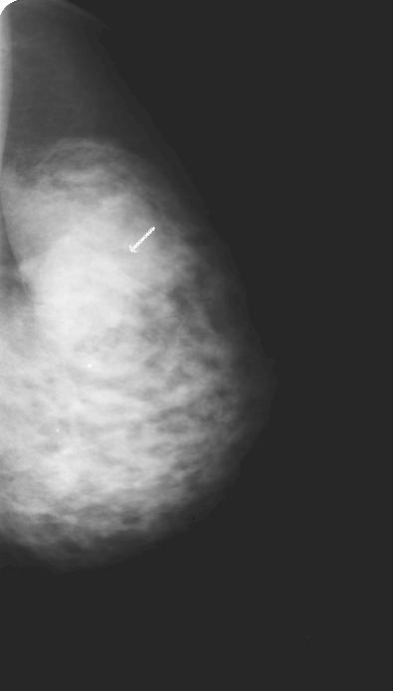

Breast Scan

Snuck into the Book in Figure 6.2 however, was a set of mammograms with breast density scores - see the image on the left.